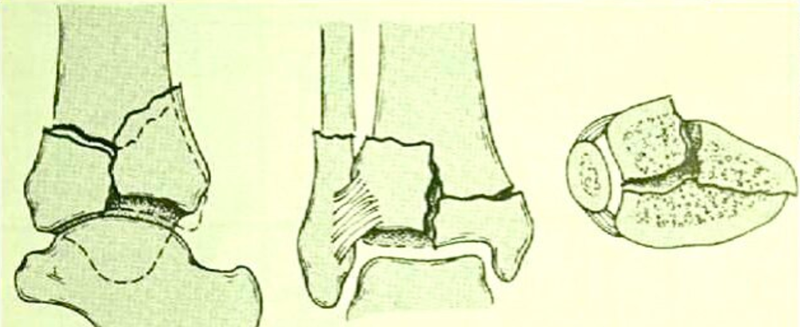

图3 Ⅰ型:没有移位的踝关节劈裂骨折

图4 Ⅱ型:轻度嵌压或粉碎的移位骨折

图5 Ⅲ型:严重的关节面粉碎和干骺端嵌压的移位骨折